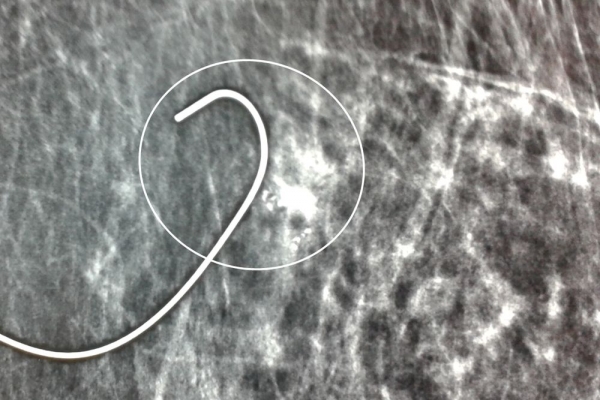

Σε περίπτωση που απαιτείται η χειρουργική αφαίρεση ενός ευρήματος που δε ψηλαφάται από το χειρουργό, τότε γίνεται η τοποθέτηση αγκίστρου σήμανσης (hook) λίγο πριν το χειρουργείο. Το άγκιστρο έχει σκοπό να καθοδηγήσει το χειρουργό για την αφαίρεση του σωστού τμήματος του μαστού, ώστε να αφαιρεθεί με ασφάλεια η ύποπτη βλάβη χωρίς να επηρεασθεί η αισθητική εικόνα του μαστού, πράγμα πολύ σπουδαίο ειδικά σε νέες γυναίκες και σε γυναίκες με μικρό μαστό.